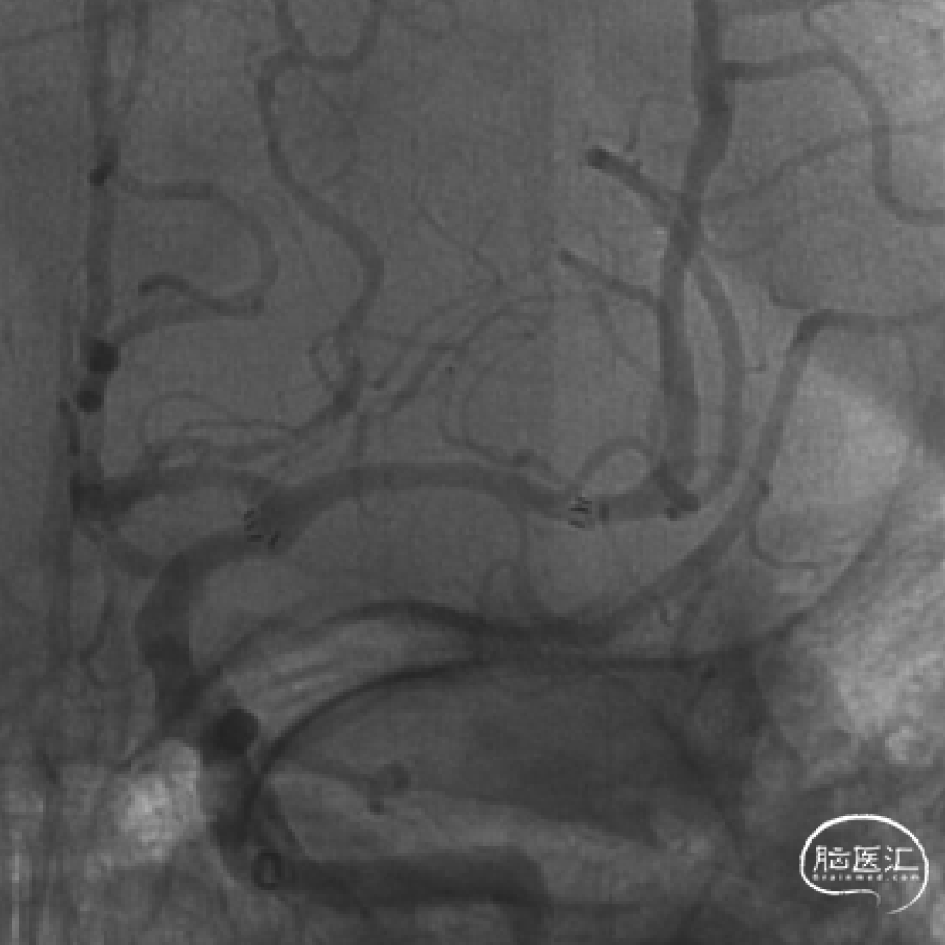

术中造影

术后即刻支架内血流通畅,无残余狭窄

术后即刻eTICI3级再通

术后CT少许造影剂渗出可能,24h复查较前吸收